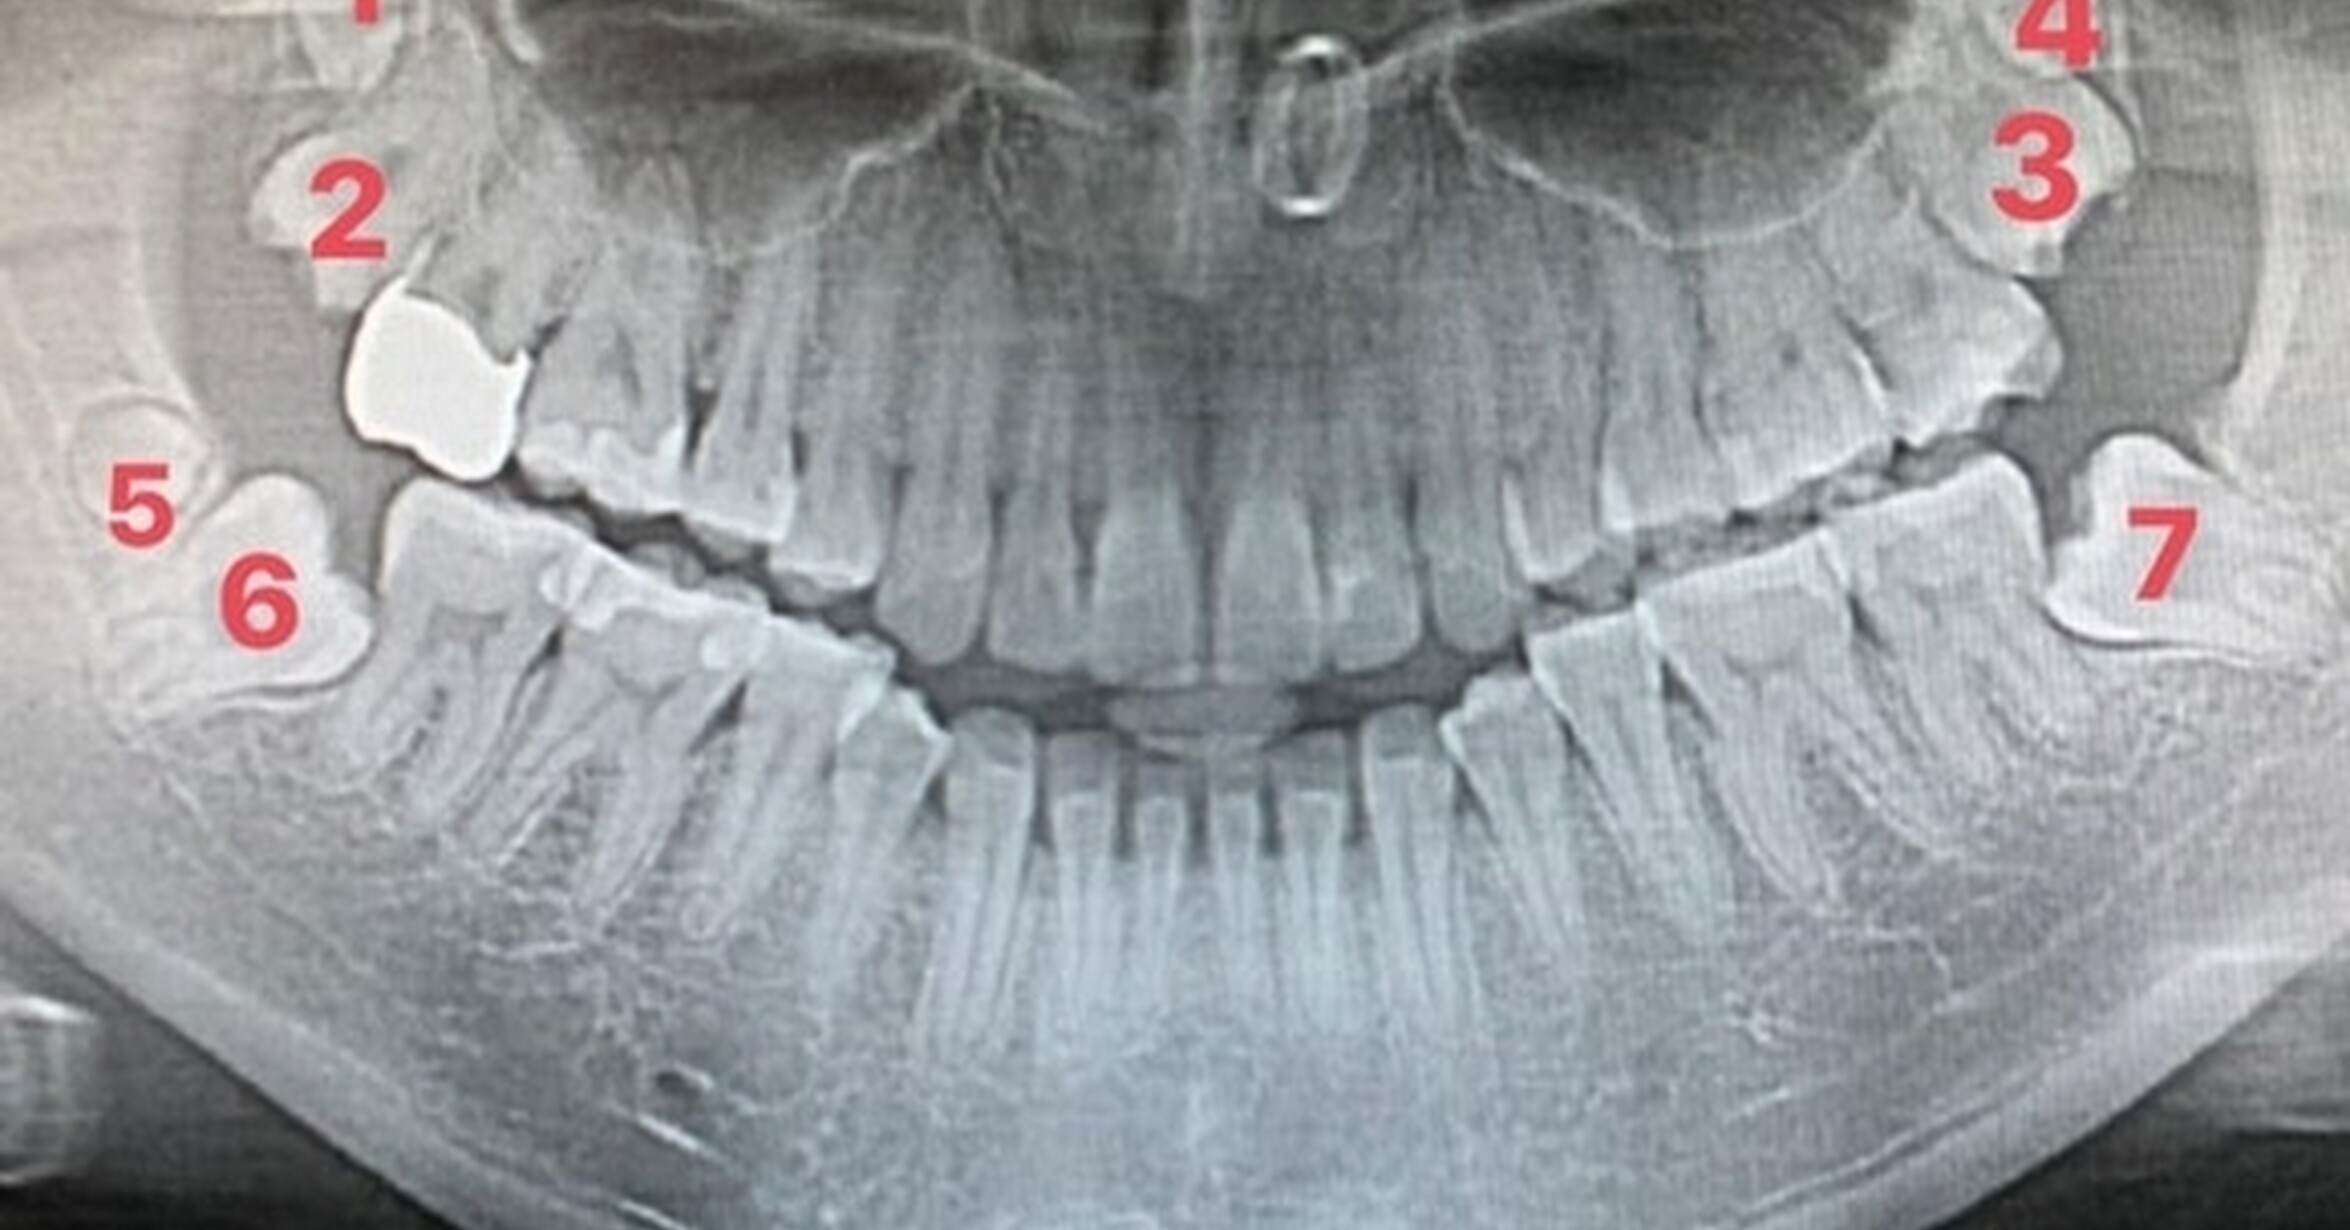

Muela Del Juicio A Los 60 Años. Muela Del Juicio A Los 60 Años, Las Cordales o Muelas del juicio, edad para extraerlas, 8.24 MB, 06:00, 257,132, Sonrilaser, 2013-06-05T16:32:08.000000Z, 3, ¿A QUÉ EDAD SALEN LAS MUELAS DEL JUICIO? – COED, www.coed.mx, 1024 x 536, jpeg, WebLa edad normal de erupción de los terceros molares son los 18 años, aunque es verdad que hay bastante variabilidad. Además, en muchos casos las muelas del. WebMuelas del juicio a los 40. Se llaman así ya que a la edad que suelen aparecer, las personas tienen el juicio más desarrollado, que en el tiempo en que salen las anteriores., 20, muela-del-juicio-a-los-60-anos, Reseñas de alimentos y noticias